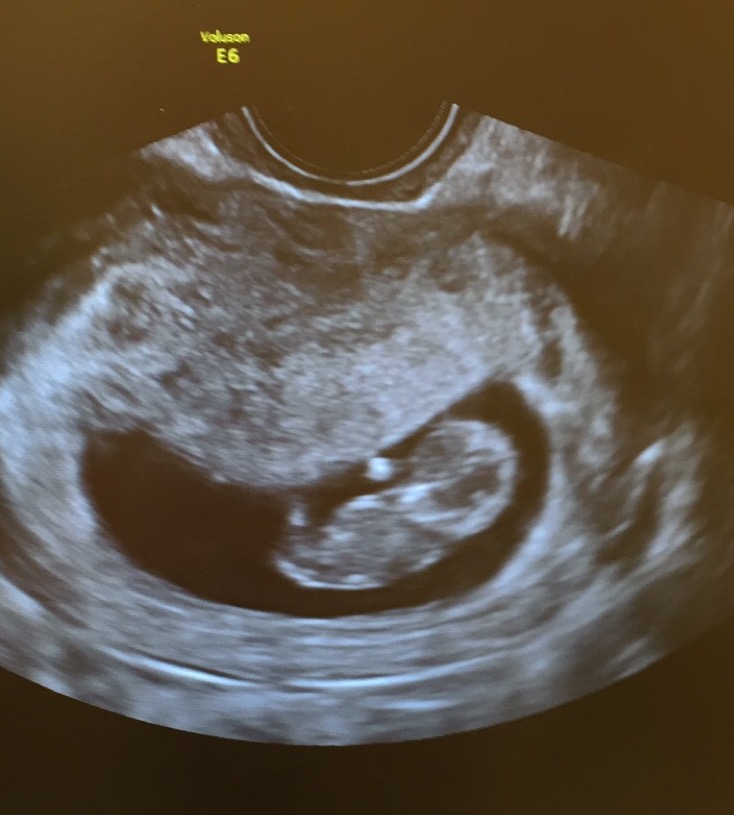

Transferred to the OB and got a external scan. Didn't think he'd do another one but I was so excited to see the LO again, and it's grown so much in just 4 days! This is 8+4!